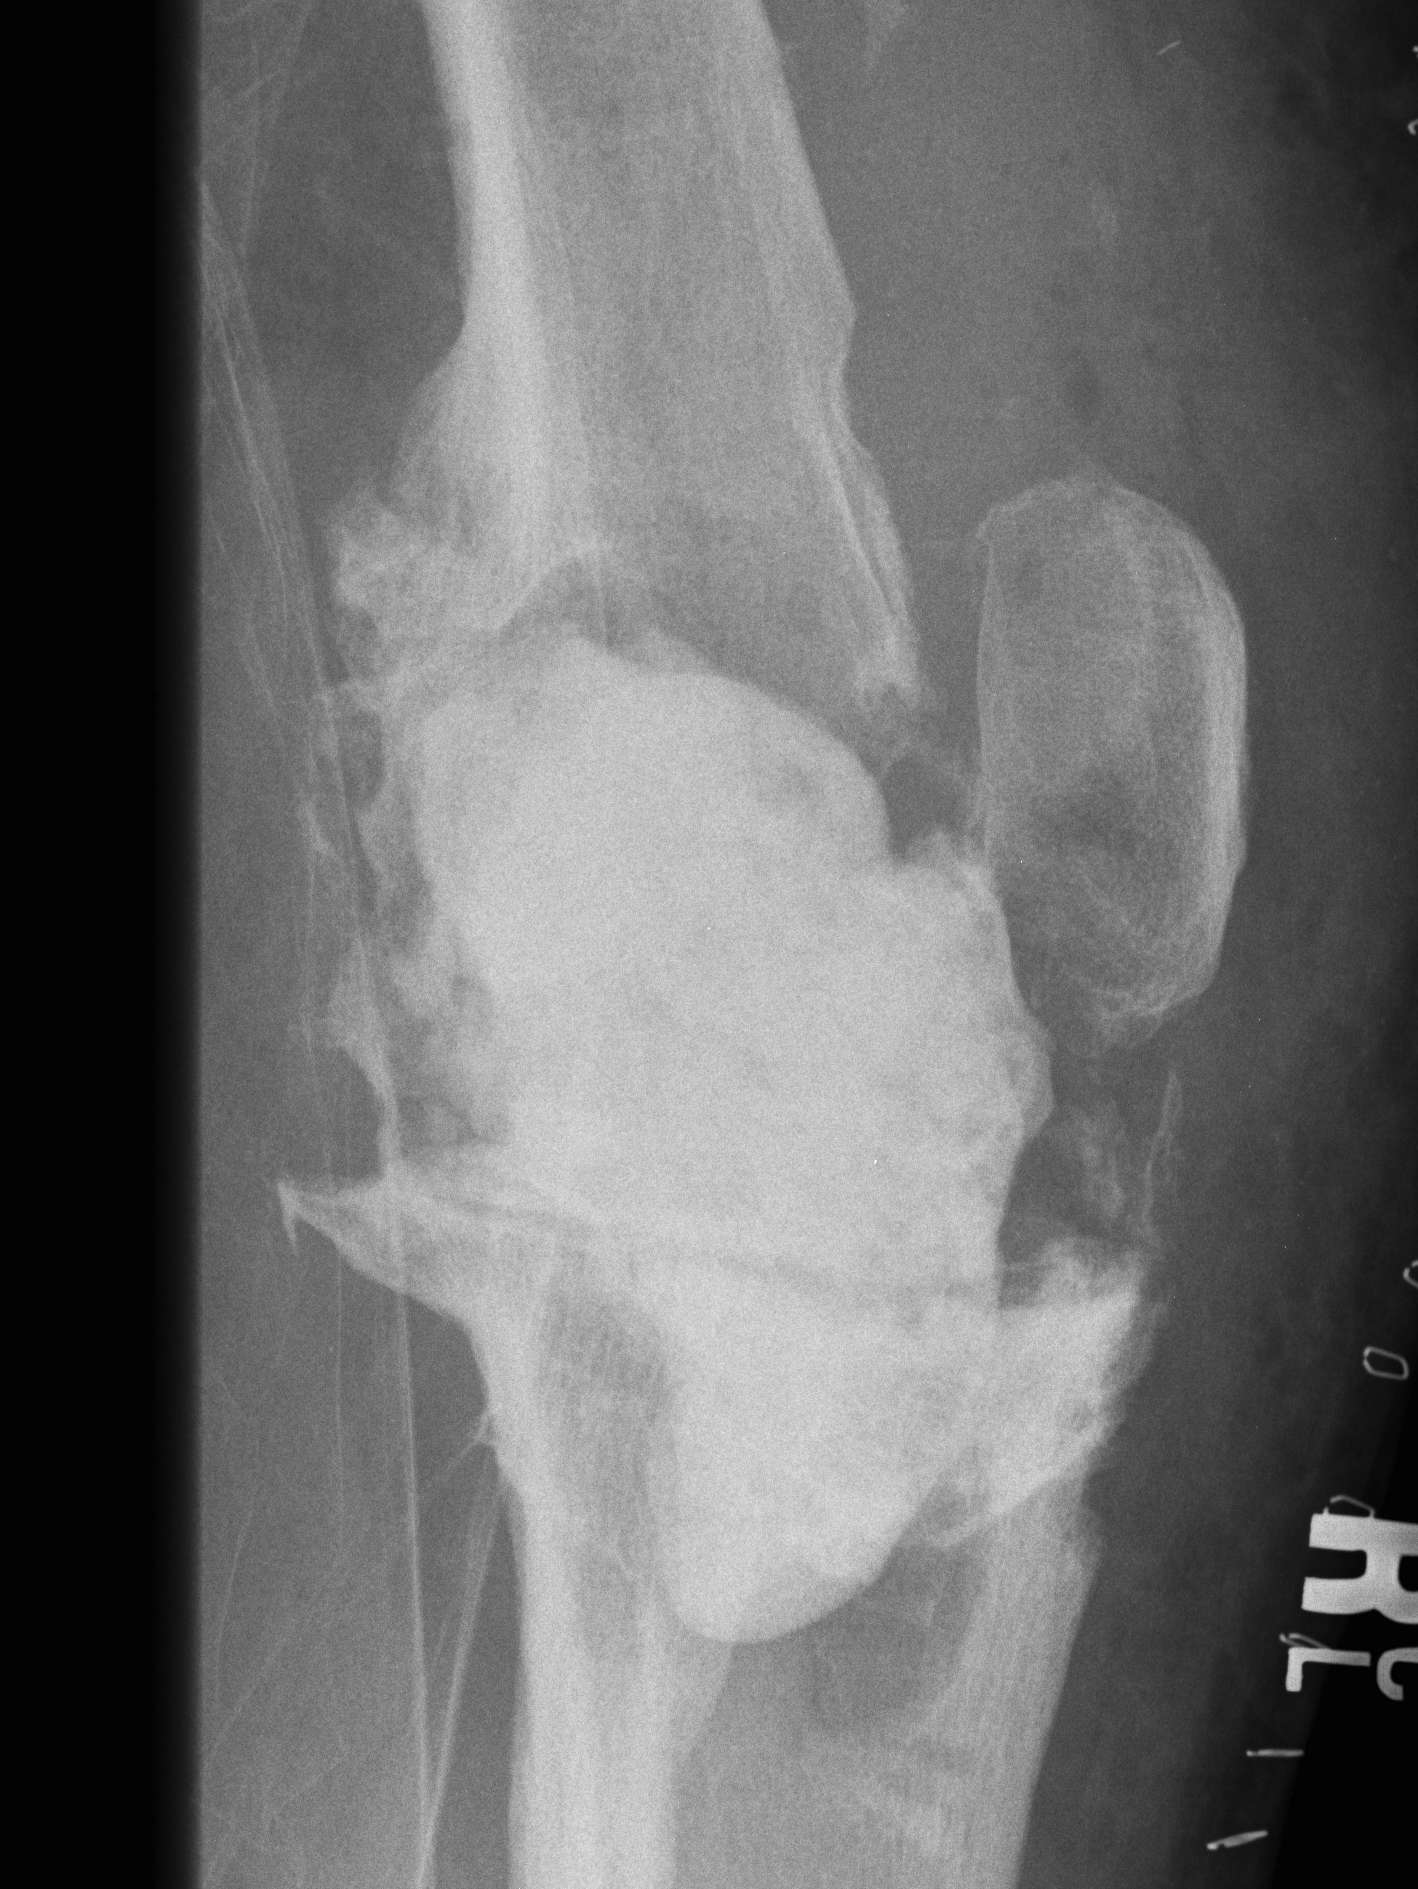

Xray

- progressive early lysis